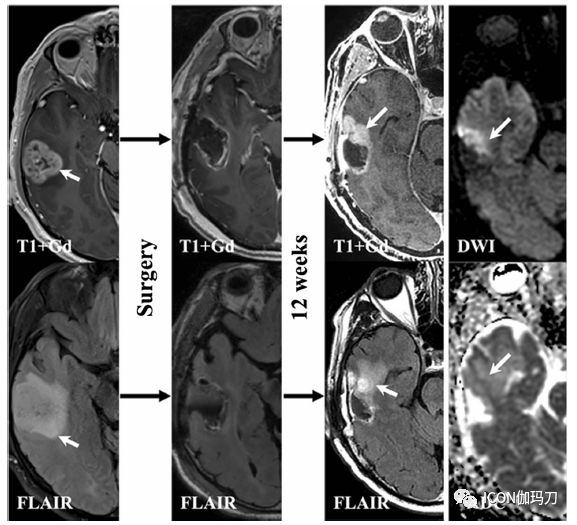

图5 假性进展。来自一例诊断为右侧颞叶胶质母细胞瘤IDH-野生型病人的序列图像。在左边的列中,基线MRI扫描显示不均匀增强,界限不清,中央坏死性肿块,位于右侧颞叶中央,周围FLAIR高信号与胶质母细胞瘤相对应。第二列对应的是术后即刻扫描,显示肿瘤增强和非增强部分的肉眼全切除。第三列对应于完成标准治疗后12周随访MRI扫描显示一个令人忧虑的新的增强区域和FLAIR高信号,沿手术瘤床的前缘(箭头)。在DWI和ADC图像上无相关的限制性扩散。病理检查证实新的增强部位对应治疗变化(假性进展)

对药物治疗难治的脑放射性坏死可能需要手术干预以减轻肿块占位效应(图5)。尽管手术切除,坏死病灶以外的水肿可能需要几周的时间才能解决,应该进行密切监测。此外,手术可以提供组织诊断,以及研究样本排除肿瘤进展的能力,可能会在活检时被疏漏。重要的是,明智地选择外科手术适应的患者,因为病人往往经大量预处理,有多种合并症,且可能有一个不好的性能状态,这使他们有手术并发症发生率的高风险,特别是与伤口有关的并发症和潜在死亡率。理想的外科适应的患者,应该具有良好的性能状态,可到达坏死肿块的位置,合并症最低程度或无,还有一例药物治疗失败。